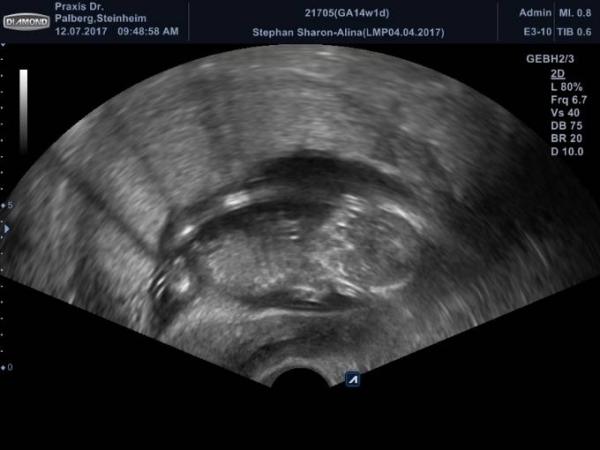

Hallo ihr Lieben Ich bin zurück alles ist in Bester Ordnung ich bin so froh. Mein Gyn sagte erst da sieht man es schön sie bekommen ein Mädchen und dann war er sich doch nicht mehr sicher und ist wieder zurück gerudert, naja Hauptsache alles ist in Ordnung.

Bild zu Zurück vom FA und 70% outing - Forum für Januar - Mamis